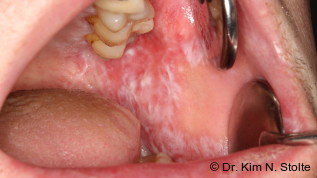

HPV-induzierte Läsionen im Bereich des retromolaren Trigonums, wie Papillome, Leukoplakien oder orale Plattenepithelkarzinome treten vergleichsweise selten auf. Der Übergang von orthokeratinisierter Gingiva zu nicht verhornender Mundschleimhaut, bei teils abnormer Lage retinierter oder teilretnierter Weisheitszähne mit klinisch und radiologisch erkennbaren Pathologien, charakterisiert diese Region.15

In der Literatur sind wenige Studien über Läsionen im Bereich des rTR beschrieben. Peters et al. publizierten 2017 eine Arbeit über das Auftreten eines warzigen Dyskeratom des rTR.21 Dabei berichten sie in ihrer Studie, dass diese seltene Läsion vorrangig Bereiche keratinisierter Mundschleimhaut befällt, das rTR jedoch von nicht verhornender Mukosa bedeckt ist.21 Wie oben bereits beschrieben, ist die Basis des rTR von Gingiva des Alveolarkamms bedeckt und folglich der mastikatorischen Schleimhaut mit verhornendem Epithel zuzuordnen.18 Somit gilt das rTR als eine anatomisch relevante Region für das Auftreten HPV-induzierter Läsionen.

Hierbei wird in der Literatur von epithelialen Nischen gesprochen. Manche dieser Epithelien weisen Besonderheiten auf, wie die Krypten der Tonsillen, Speicheldrüsen der Mundschleimhaut oder Schweißdrüsen der Haut, die zu Unterbrechungen der intakten Barriere der Plattenepithelien führen und es den Viren erleichtern, diese Nischen zu befallen. Manche HPV-Typen, vor allem die HR-HPVs, befallen vorrangig Transformationszonen. Das sind Abschnitte, bei denen bspw. orthokeratinisiertes mehrschichtiges Plattenepithel an Zylinderepithel grenzt. Es wird davon ausgegangen, dass an Grenzen, wie die Endocervix an die Ectocervix, epitheliale Zellen unterschiedlich auf den viralen Befall reagieren und eine Infektion erleichtern können.7 Der Übergang von Mundhöhle zum Pharynx bildet ebenfalls eine epitheliale Nische für HR-HPV-Typen, wonach sich in Gebieten wie der Zunge, der Gaumen oder das rTR OCSCCs bilden können.8

Wie oben bereits aufgeführt, zählen OCSCC des rTR mit circa neun Prozent zu vergleichsweise seltenen, jedoch wegen ihrer Nähe zu wichtigen anatomischen Nachbarstrukturen und deren Invasion, zu sehr gefährlichen Tumoren. Mit einer Überlebensrate von 97 Monaten stellt diese Tumorentität eine außerordentliche chirurgsich-therapeutische Herausforderung dar.22 Die Früherkennung suspekter Läsionen des rTR und die regelmäßige Kontrolle mittels Bürstenbiopsien sind eminente Bausteine in der Prävention bzw. Früherkennung von oralen Karzinomen.

Vor allem im Bereich des rTR sind durch Schlupfwinkel und chronischen Infektionen teilretinierter Weisheitszähne, langanhaltende Störungen der Barrierefunktion des Epithels gegeben und ermöglichen eine bakterielle und virale Besiedlung. Folglich könnte die retromolare Gingiva bei persistierenden Infektionen, wie einer Perikoronitis, als Reservoir für Humane Papillomaviren dienen und im Laufe der Infektion tiefere anatomische Gebiete, wie Pharynx oder Larynx, befallen und gutartige Läsionen bis hin zu SCCs verursachen. Bei bis zu 80 Prozent der jungen Erwachsenen lässt sich mindestens ein retinierter Weisheitszahn diagnostizieren. Allein 20 bis 60 Prozent aller retinierten und teilretinierten Weisheitszähne zeigen perikoronare Pathologien (z. B. Perikoronitis oder Dentitio difficilis), wodurch die operative Weisheitszahnentfernung zu den häufigsten ambulant durchgeführten chirurgischen Eingriffen zählt.15

In der nächsten Ausgabe wird ein Patientenfall vorgestellt, bei dem nach Osteotomie der Weisheitszähne im Unterkiefer und histologischer Untersuchung des perikoronaren Gewebes histologische Merkmale einer HPV-Infektion des rTR gefunden werden konnten.